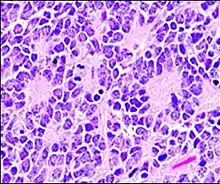

A Homer Wright pseudorosette is a type of pseudorosette in which differentiated tumor cells surround the neuropil.[15] Examples of tumors containing these are neuroblastoma, medulloblastoma, pinealoblastoma, and primitive neuroectodermal tumors of bone. Homer Wright rosettes are considered "pseudo" in the sense that they are not true rosettes. True rosettes are Flexner–Wintersteiner rosette, which contain an empty lumen. Homer Wright rosettes contain abundant fibrillary material. They are named for James Homer Wright.

Structure of a Homer Wright pseudorosette